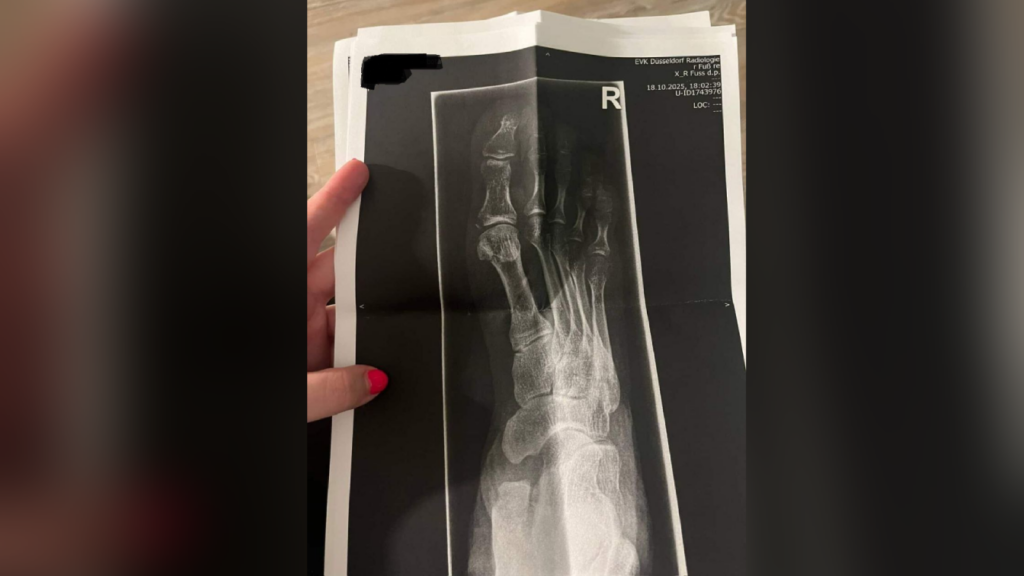

Первое время Айхал и Бота общались по переписке, но потом развиртуализировались — девушка дважды приезжала в Дюссельдорф, куда Айхал переехал после освобождения. Второй визит, произошедший в октябре 2025 года, закончился для девушки переломом ноги.

«Айхал напился вином и напал на меня — начал душить, а когда я вырвалась, стал пинать меня, — говорится в ее посте. — Всем весом он наступил мне на лодыжку и сломал ее. Мне пришлось ехать в Дюссельдорфскую больницу делать рентген, мне наложили гипс. Перелом оказался со смещением, поэтому нужна была операция. Сейчас в Алматы я восстанавливаюсь после перелома и операции».